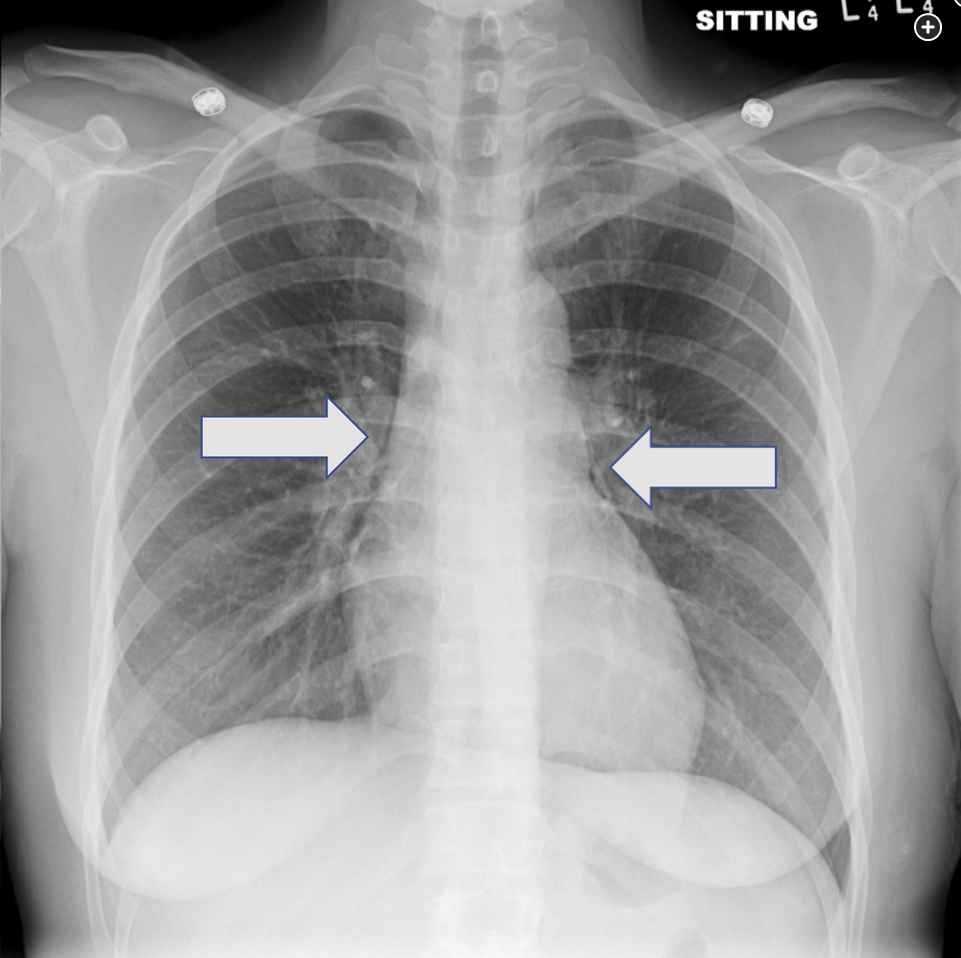

This patient’s chest radiographs reveal a pneumomediastinum, which in the clinical context of protracted vomiting raises reasonable concern for esophageal rupture (Boerhaave’s syndrome). Assessment for possible esophageal leak by fluoroscopic study would be the next appropriate step. When this study was performed (Figure 6), an esophageal leak was identified, and the patient was taken for emergent surgical repair. CT scanning can also be helpful to determine the extent of injury.

Spontaneous esophageal rupture can occur during forceful retching and often presents acutely with vomiting, chest pain, and subcutaneous emphysema (Mackler’s triad) or some other manifestation of barotrauma in the chest (as in this case). Severe vomiting in an alcoholic is a common setting for injury. In the great majority of cases, the esophageal tear is linear, located in the distal esophagus just above the gastroesophageal junction, and in a posterolateral position. Given this location, left pneumothorax may be seen on the chest radiograph, and as the contaminated mediastinal and pleural spaces progress with infection, left pleural effusion is common. If thoracentesis is performed, the pleural fluid is exudative, with a low pH and extremely high amylase level, the latter related to saliva spillage. Once mediastinal and pleural infection become entrenched, which happens quickly, sepsis and high mortality characterize this process. Accordingly, early diagnosis and repair are imperative. In most cases, definitive repair by thoracotomy is pursued, but in some cases stenting via endoscopy is an option.12345